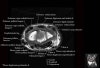

- Coronal section

Coronal T1 imaging evaluates bone marrow signal (ex. increased in avascular necrosis) and the relationship of the osseous structures to each other (ex. scapholunate disassociation).